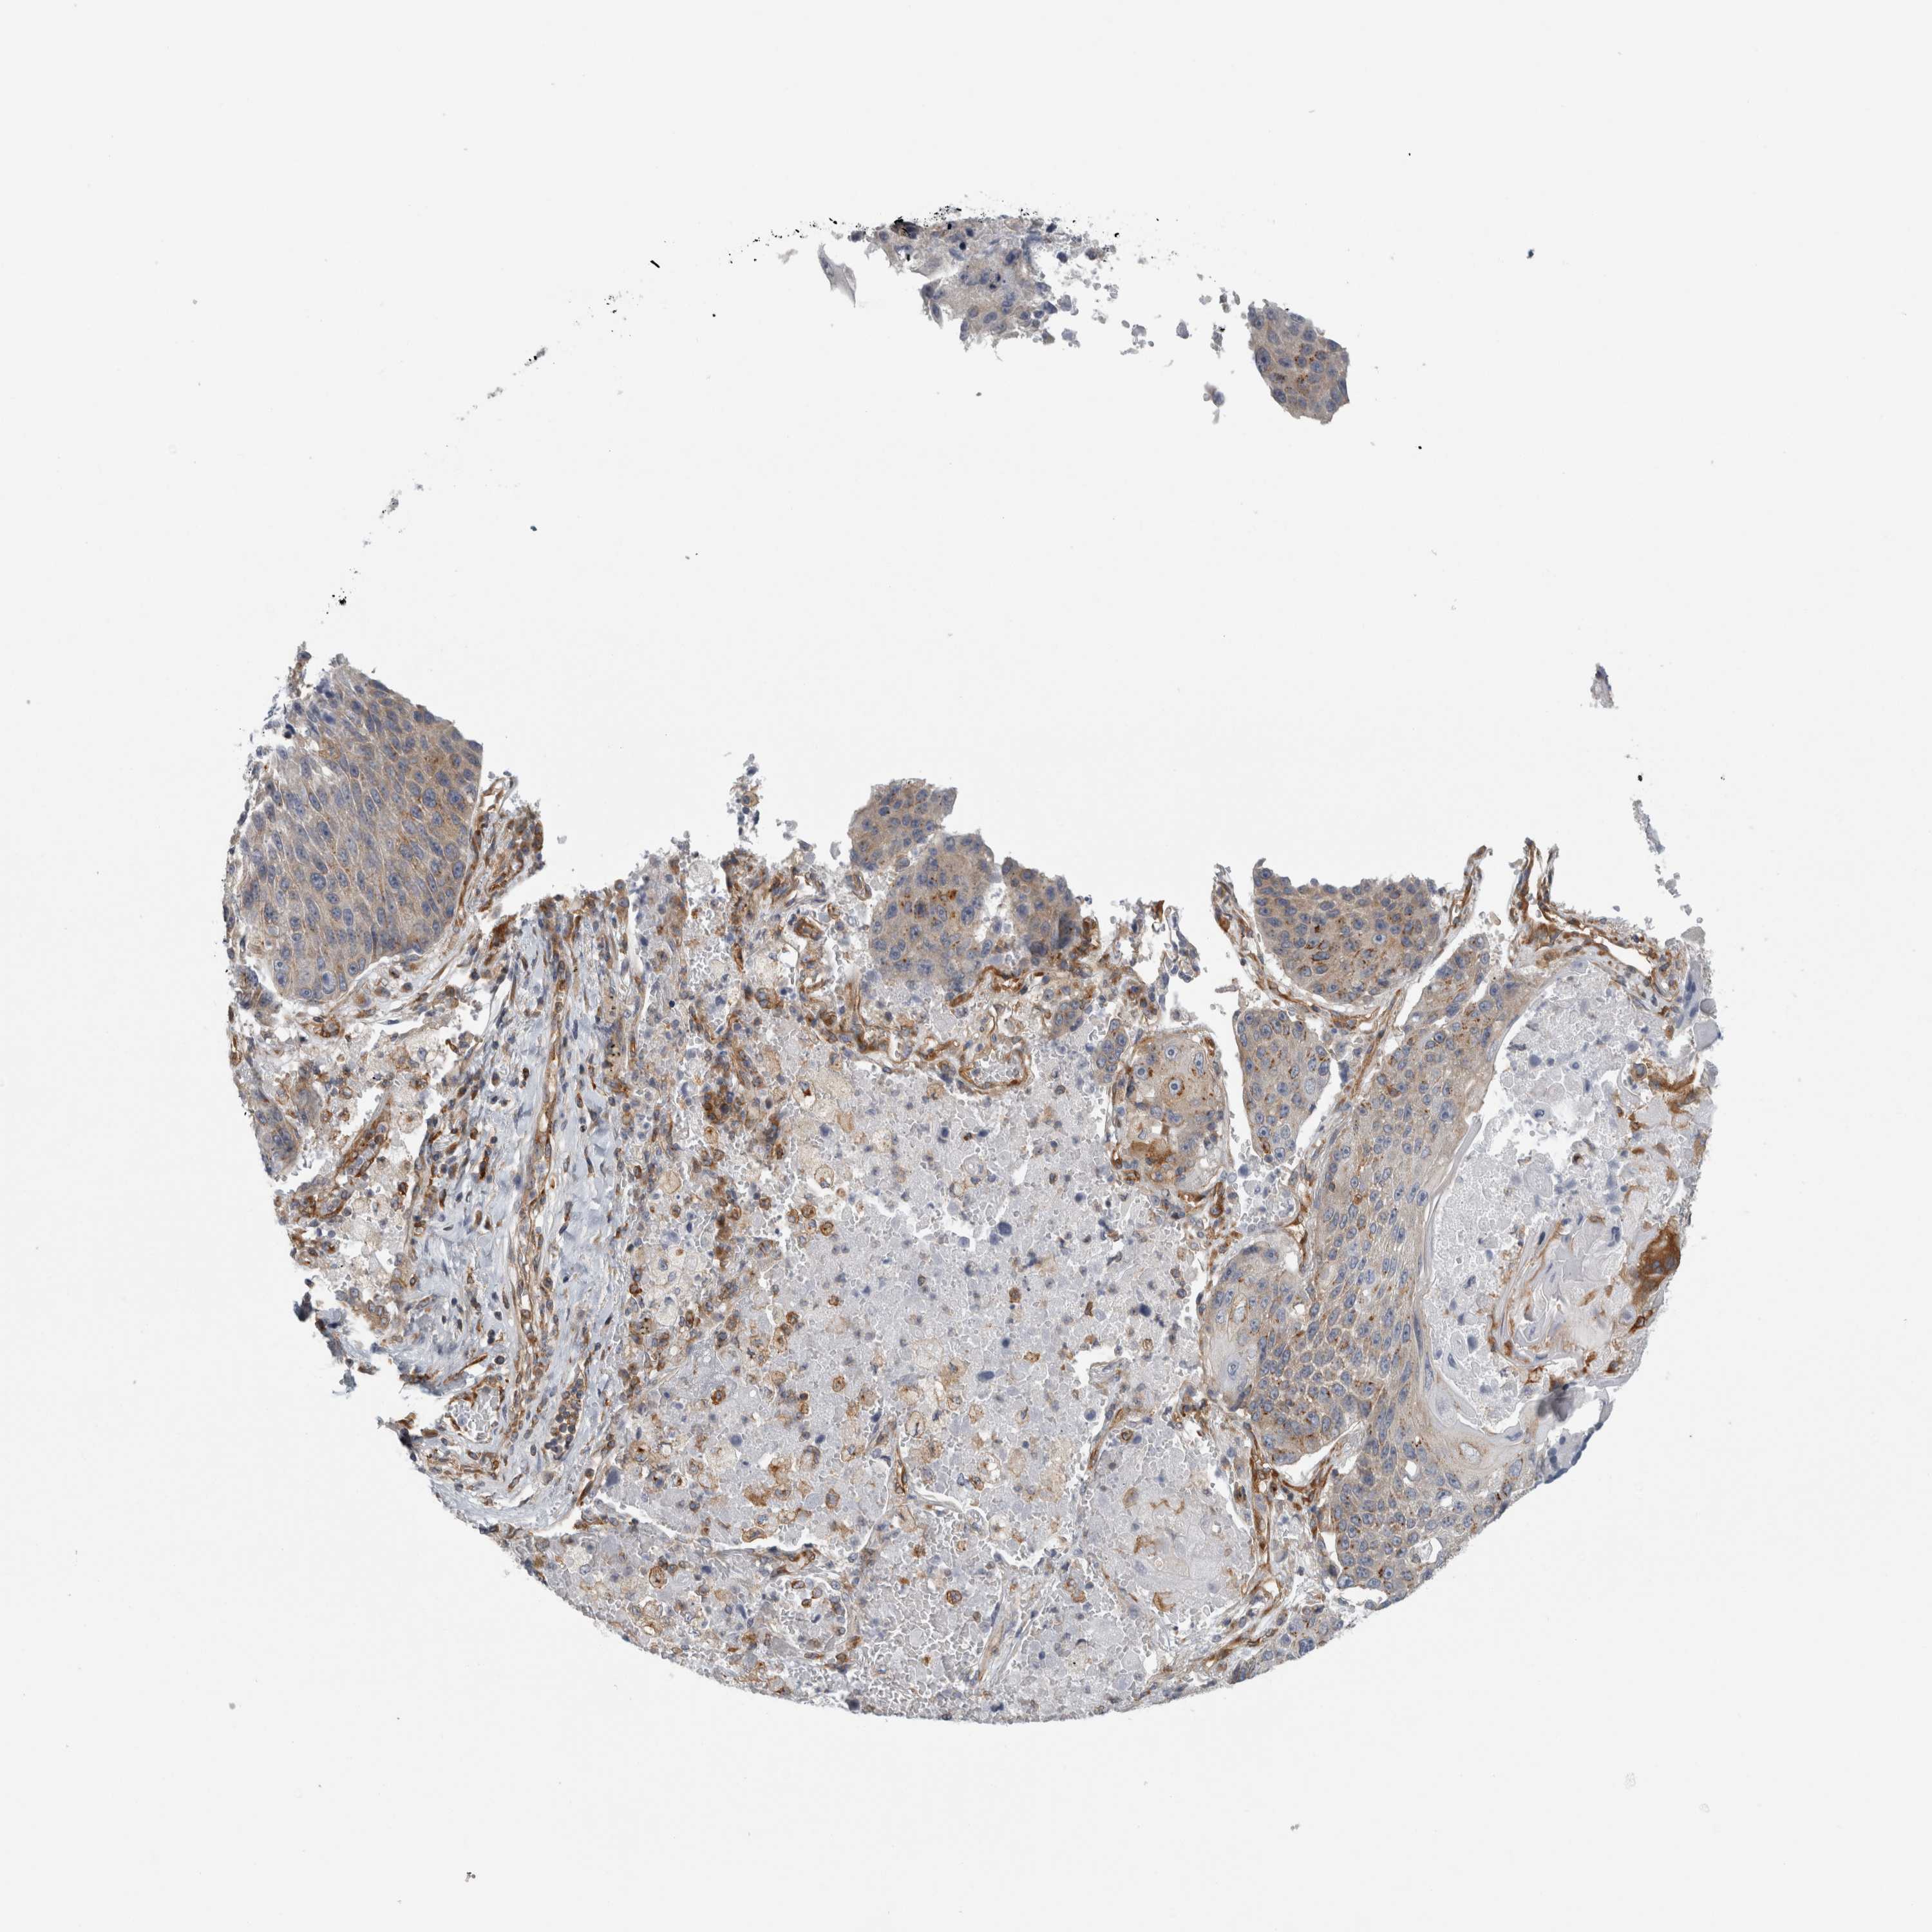

CANCER LUNG CANCER Show tissue menu

LUAD TCGA LUAD VALIDATION LUSC TCGA LUSC VALIDATION PROTEIN LUAD CPTAC PROTEIN LUSC CPTAC PROTEIN EXPRESSION